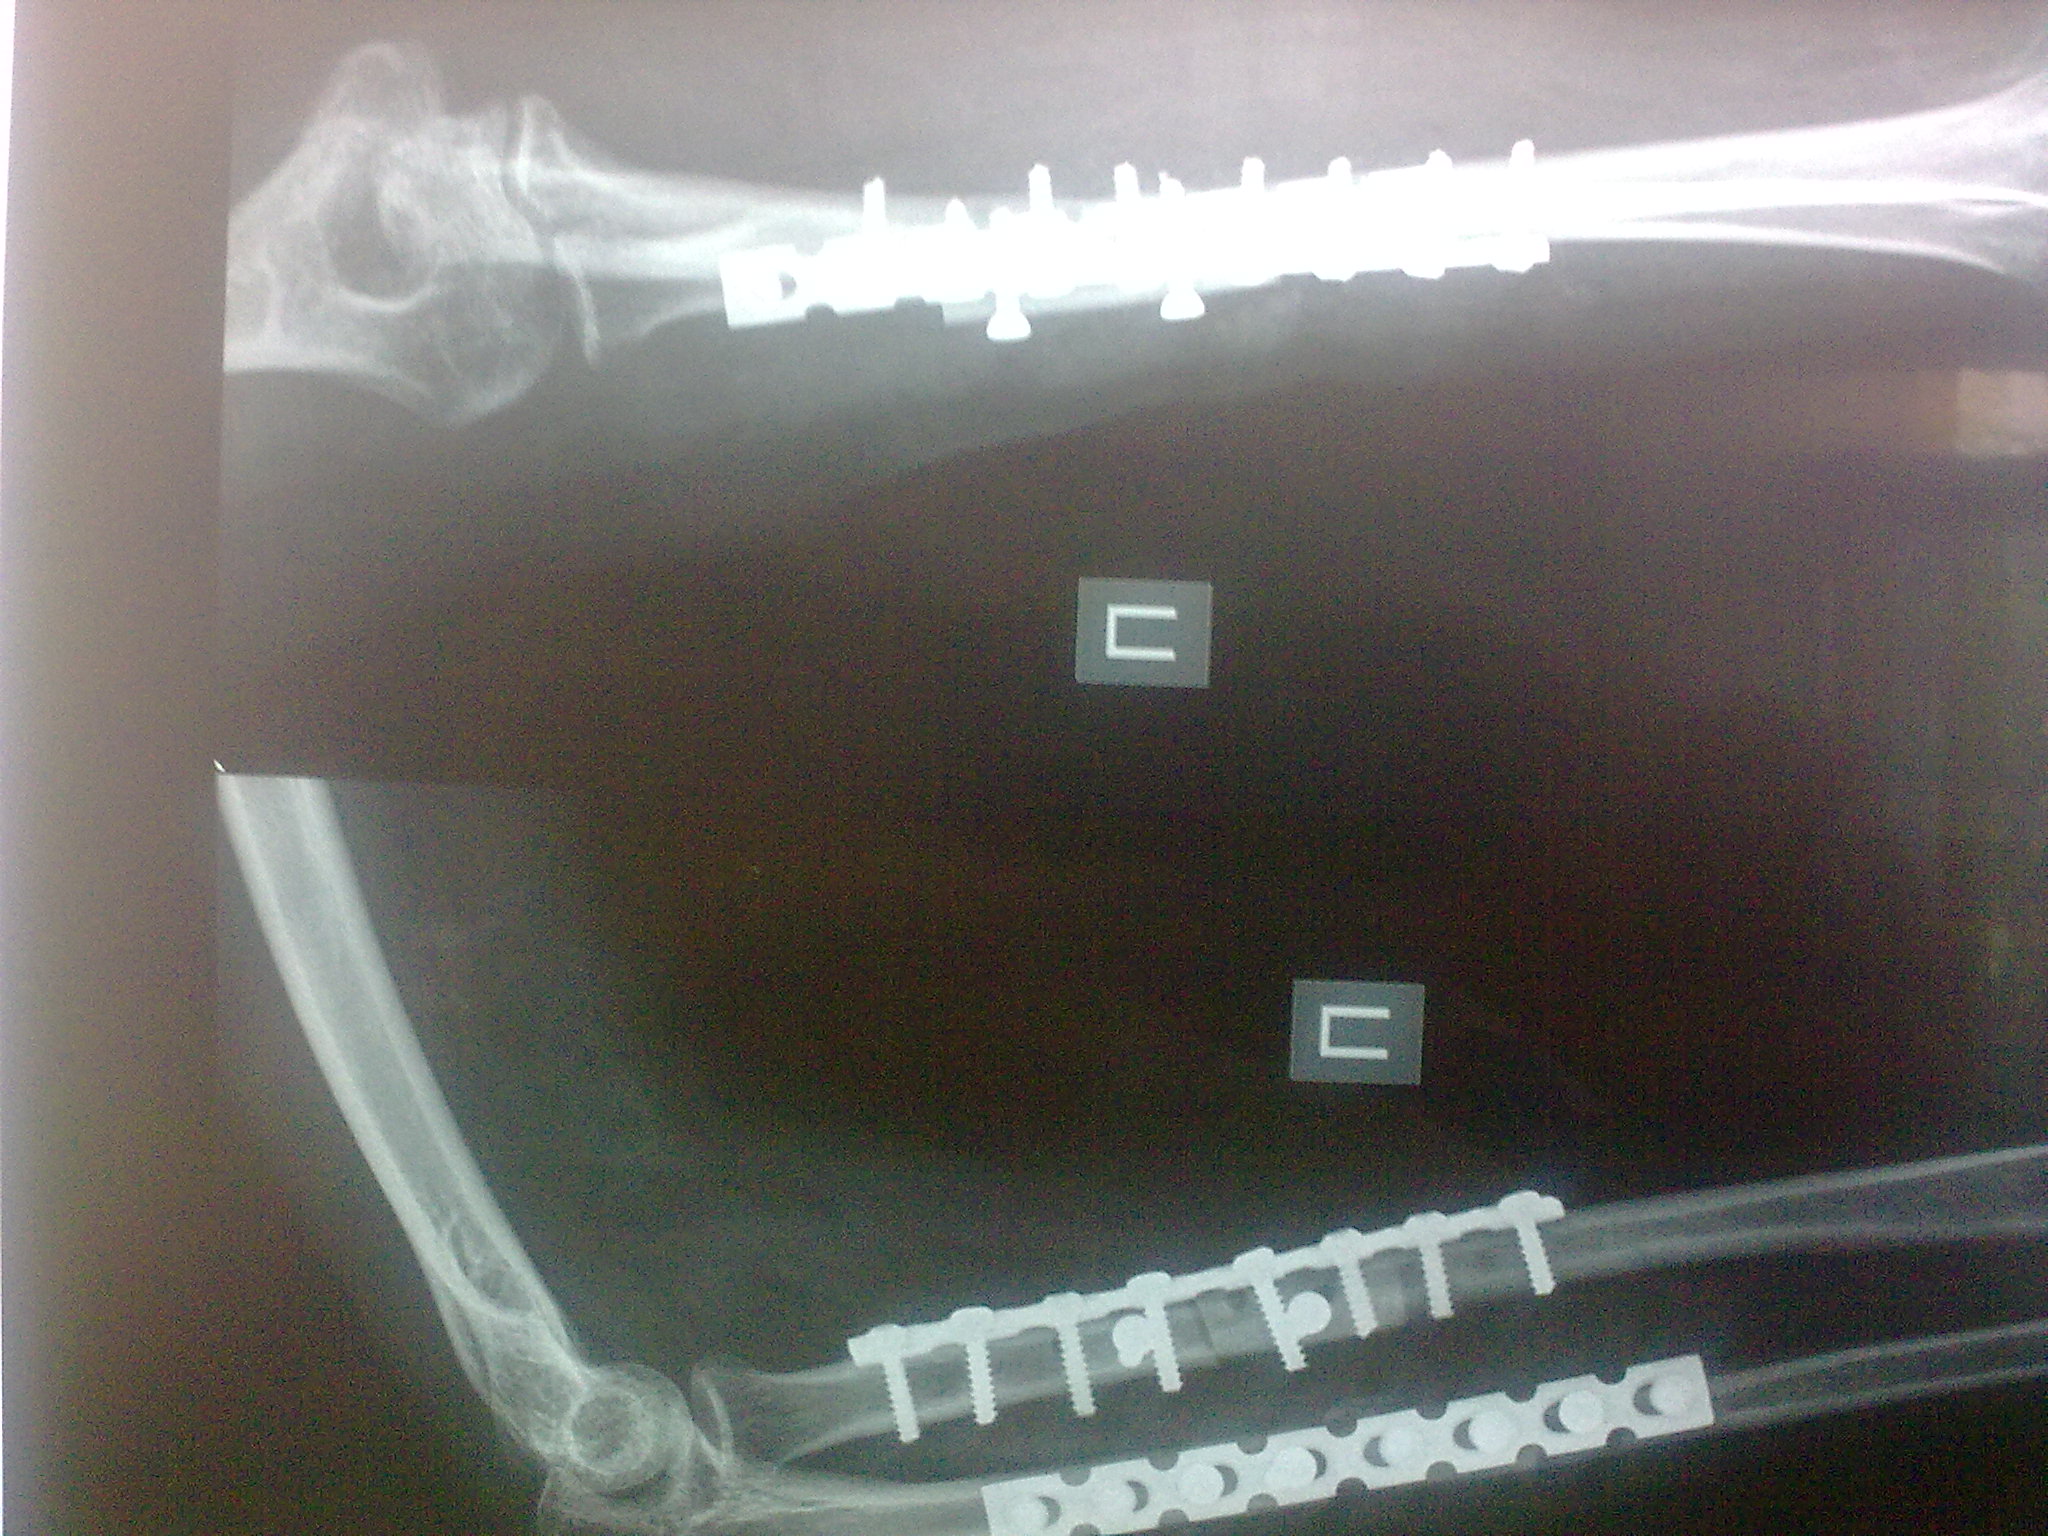

Пациентка С. 23 лет. В марте 2009 года операция остеосинтез костей предплечья пластинами по поводу оскольчатого перелома.

04.07.09. при совершении супинационных движений предплечья ощутила хруст (низкоэнергетическая травма). На рентгенограммах несросшийся перелом костей предплечья, перелом конструкций. Коллеги подскажите что делать, поделитесь опытом.

Что же произошло в данном случае? В основе любой неудачи внутренней фиксации лежат или биологические, или механические причины, или же сочетание оных. В данном случае механическая причина неудачи налицо - использование 1/3 трубчатых пластин, толщина которых колеблется от 1 до 2мм, является неправомерным в лечении переломов диафиза предплечья. Данные пластины предназначены для лечения переломов лодыжек и лишь изредка используются для фиксации очень дистальных или проксимальных переломов диафиза локтевой кости. И производитель здесь не имеет определяющего значения, главное, это слишком "слабый" имплантат для лечения данного повреждения. И результат, к сожалению, закономерен.

Спасибо коллеги. Выполнили ресинтез реконструкционными пластинами с костной аутопластикой кортикальными трансплантатами с декортикацией.

Кликните для загрузки файла 16072009402[1]

611KB (625938 bytes)